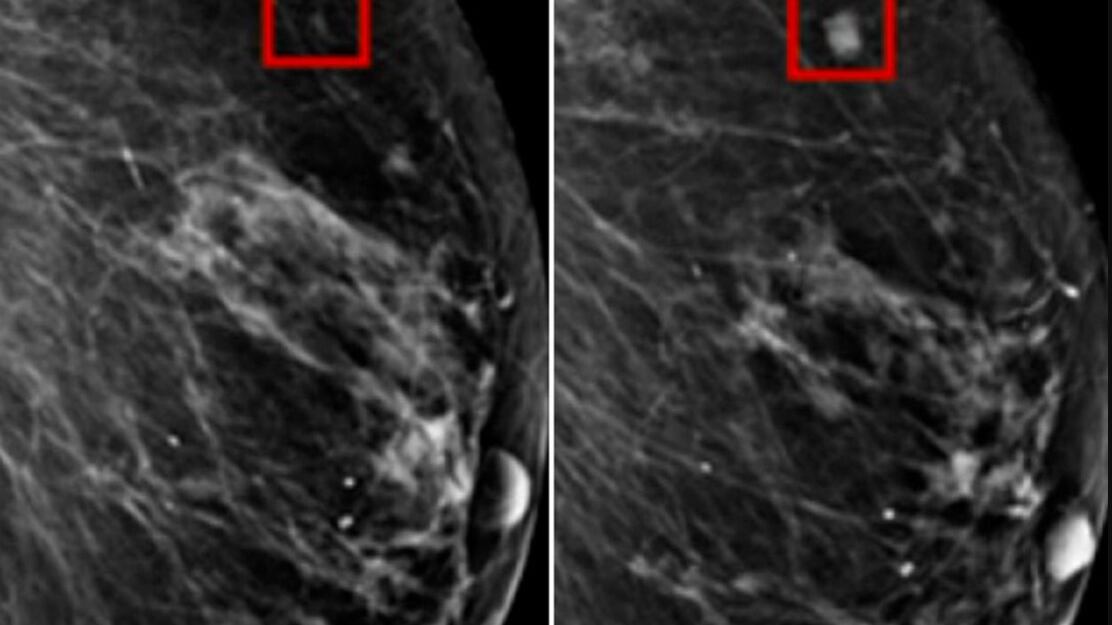

Dos radiólogos habían dicho previamente que la radiografía no mostraba ningún signo de que la paciente tuviera cáncer de mama. Pero Ambrózay estaba observando de cerca varias áreas del escaneo marcadas con un círculo rojo, que el software de inteligencia artificial había marcado como potencialmente cancerosas.

La IA, llamada Detección Asistida por Computadora, identifica manchas en las mamografías para que los médicos las inspeccionen de cerca.

Un estudio asociado del Instituto Tecnológico de Massachusetts (MIT) descubrió que la tecnología podía identificar cambios entre mamografías y detectar puntos que tenían riesgo de convertirse en cáncer. Los puntos identificados en pacientes se convirtieron en cáncer de mama años después.